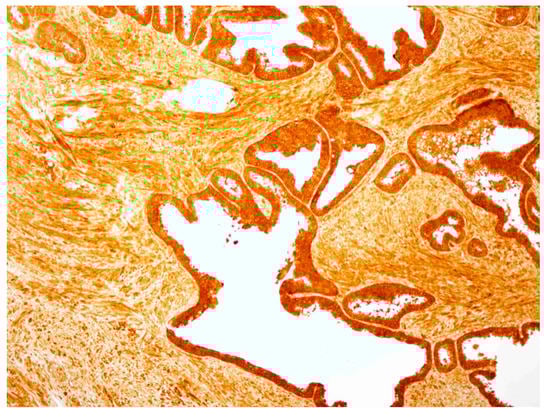

2.4. hPSA Immunohistochemistry with Biotynilated Antisense Peptide and Monoclonal Antibody

3.6. Immunohistochemical Staining of hPSA: Protocol 1 and Protocol 2

3.6.1. Protocol 1 (Standard IHC Staining Technique)

- The specimen was covered with peroxidase block, i.e., 100 μL of 0.03% hydrogen peroxide containing sodium azide (Dako, Glostrup, Denmark), and incubated for four minutes. Following this procedure, the specimen was gently rinsed with phosphate buffered saline (PBS), and placed in a fresh buffer bath.

- Primary monoclonal mouse anti-human PSA antibody (Clone ER-PR8, Code M0750; Dako, Glostrup, Denmark) was diluted with standard diluent containing 0.05 mol/L TRIS-HCl buffer and a 1% bovine serum albumin (BSA). 100 μL of primary antibody diluted in the proportion 1:100 was used to cover the specimen. After 30 min of incubation at room temperature, the specimen was gently rinsed with PBS and placed in a fresh buffer bath.

- 100 μL of HRP-labelled polymer conjugated to goat anti-mouse immunoglobulins in Tris-HCl buffer containing stabilizing protein and an anti-microbial agent (Dako, Glostrup, Denmark) was applied to cover the specimen, followed by a 30 min incubation. After 30 min of incubation, the specimen was gently rinsed with PBS and placed in a fresh buffer bath.

- The specimen was covered with 100 μL of AEC + substrate-chromogen solution for 10 min, i.e., 3-amino-9-ethylcarbazole containing hydrogen peroxide, stabilizers, enhancers and anti-microbial agent (Dako, Glostrup, Denmark). After that period the specimen was again rinsed with PBS.

- The slides were immersed in a bath of aqueous hematoxylin (Mayerr’s hematoxylin), and rinsed gently in a distilled water bath. Slides were dipped 10 times into a bath of ammonia (0.037 mol/L), and rinsed in a bath of distilled water for four minutes.

- The specimens were mounted and coverslipped with the non-aqueous permanent mounting medium Ultramount.

| Patient No.\Dilutions * | 1:10 | 1:50 | 1:100 | 1:200 | 1:500 |

|---|---|---|---|---|---|

| 1 | 0 | 1 | 2 | 0 | 0 |

| 2 | 0 | 1 | 2 | 1 | 0 |

| 3 | 0 | 2 | 3 | 1 | 0 |

| 4 | 0 | 1 | 2 | 1 | 0 |

| 5 | 0 | 1 | 3 | 1 | 0 |

| 6 | 0 | 1 | 2 | 1 | 0 |

| 7 | 0 | 1 | 2 | 1 | 0 |

| Sum of scores | 0 | 8 | 16 | 6 | 0 |